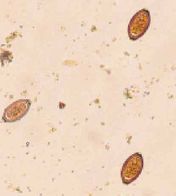

吸虫類

吸虫類